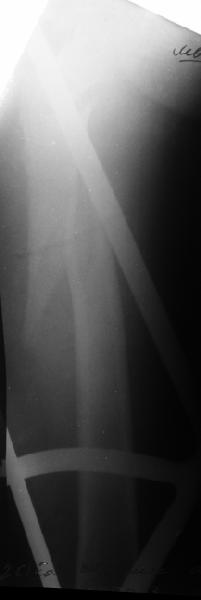

Да, сейчас это и у нас самый напрашивающийся выбор. Сделали гвоздем ChM, картинки в приложении.